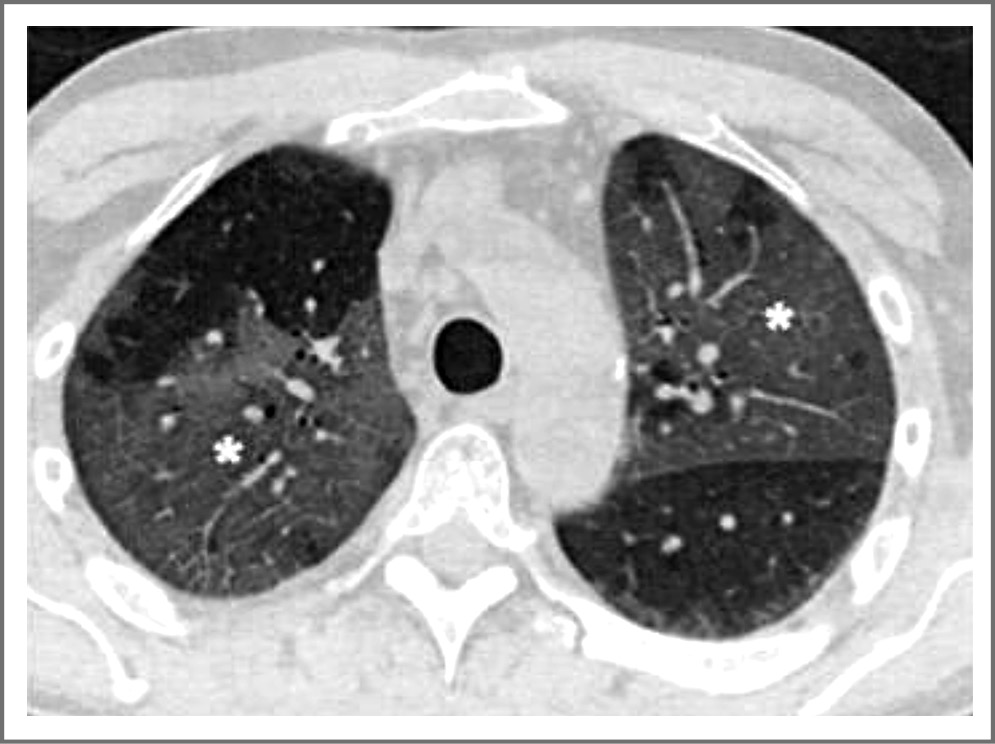

В случаях прогрессирования заболевания, как правило, это происходит на 12–14-е сутки от начала лихорадочного периода, развивается консолидация воспалительного процесса. Состояние больных COVID-19 прогрессивно ухудшается, и порой развиваются жизнеугрожающие признаки респираторного дистресс-синдрома. На рис. 2 представлена КТ больного COVID-19 на 14-е сутки от начала лихорадочного периода. В отличие от феномена «матового стекла» в консолидирующей легочной ткани не прослеживаются сосуды и просвет бронхиального дерева. Этот этап болезни связывают с гипериммунной реакцией организма человека и развитием цитокинового шторма, который предшествует респираторному дистресс-синдрому.

Рис. 2. КТ органов грудной клетки больного COVID-19 на 14-е сутки от начала лихорадочного периода, участки консолидации легочной ткани. / Fig. 2. CT organs of the chest of the patient COVID-19 on the 14th day from the beginning of the feverish period, sections of the consolidation of pulmonary tissue.